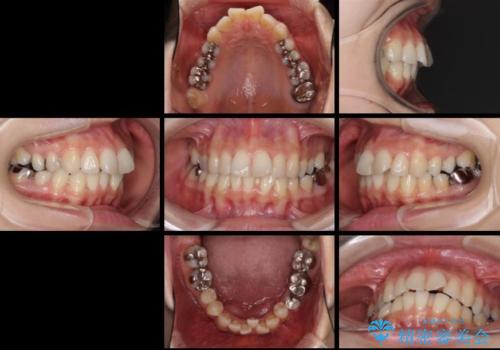

- 上下のデコボコと奥歯の咬みにくさを気にして来院された患者様です。

上顎骨の幅が下顎骨よりも小さいので、拡大装置により骨幅を広げて上下関係を改善し、その後インビザラインにて歯並びを整えることとしました。

上下の骨幅を改善したことで、スムーズに歯列矯正を行うことができました。

矯正治療中に近医で銀歯を外す治療を開始したため、治療後に奥歯の咬み合わせが不十分ですが(こちらは近医での治療により改善するとのこと)、歯列と咬み合わせが改善され、患者様には大変満足していただきました。